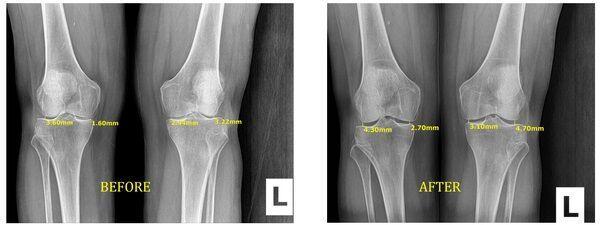

Stem cell regeneration therapy is a groundbreaking new therapy option for people with different types of joint, muscle, cartilage, ligament injuries and pain. Before you opt for surgery, consider a less invasive approach to help regenerate damaged tissue through stem cell therapy injections.

Since joint degeneration involves the breakdown of cartilage, injections involving growth factors, proteins, amino acids, a matrix of collagen (a collective tissue found in the body), hyaluronic acid, and stem cells, all of which aid in the repair of a joint. The combination of these cells create the scaffolding necessary to repair and build new cells and accelerate the body's healing potential to repair damaged tissue.

While some extreme cases may still require surgery, the majority of patients can return to a normal life shortly after the conclusion of the injections.

once a patient undergoes injections as part of the regenerative therapy program, the patient will begin to see the results. A typical patient is able to return to normal activity shortly after the therapy is completed. This means that patients do not have to deal with anesthesia. They also do not have to suffer through a long and intensive rehabilitation process. The Therapy is usually one injection, but sometime will required more. This is something a physician can better explain to the patient on a case basis before the patient consents to treatment.